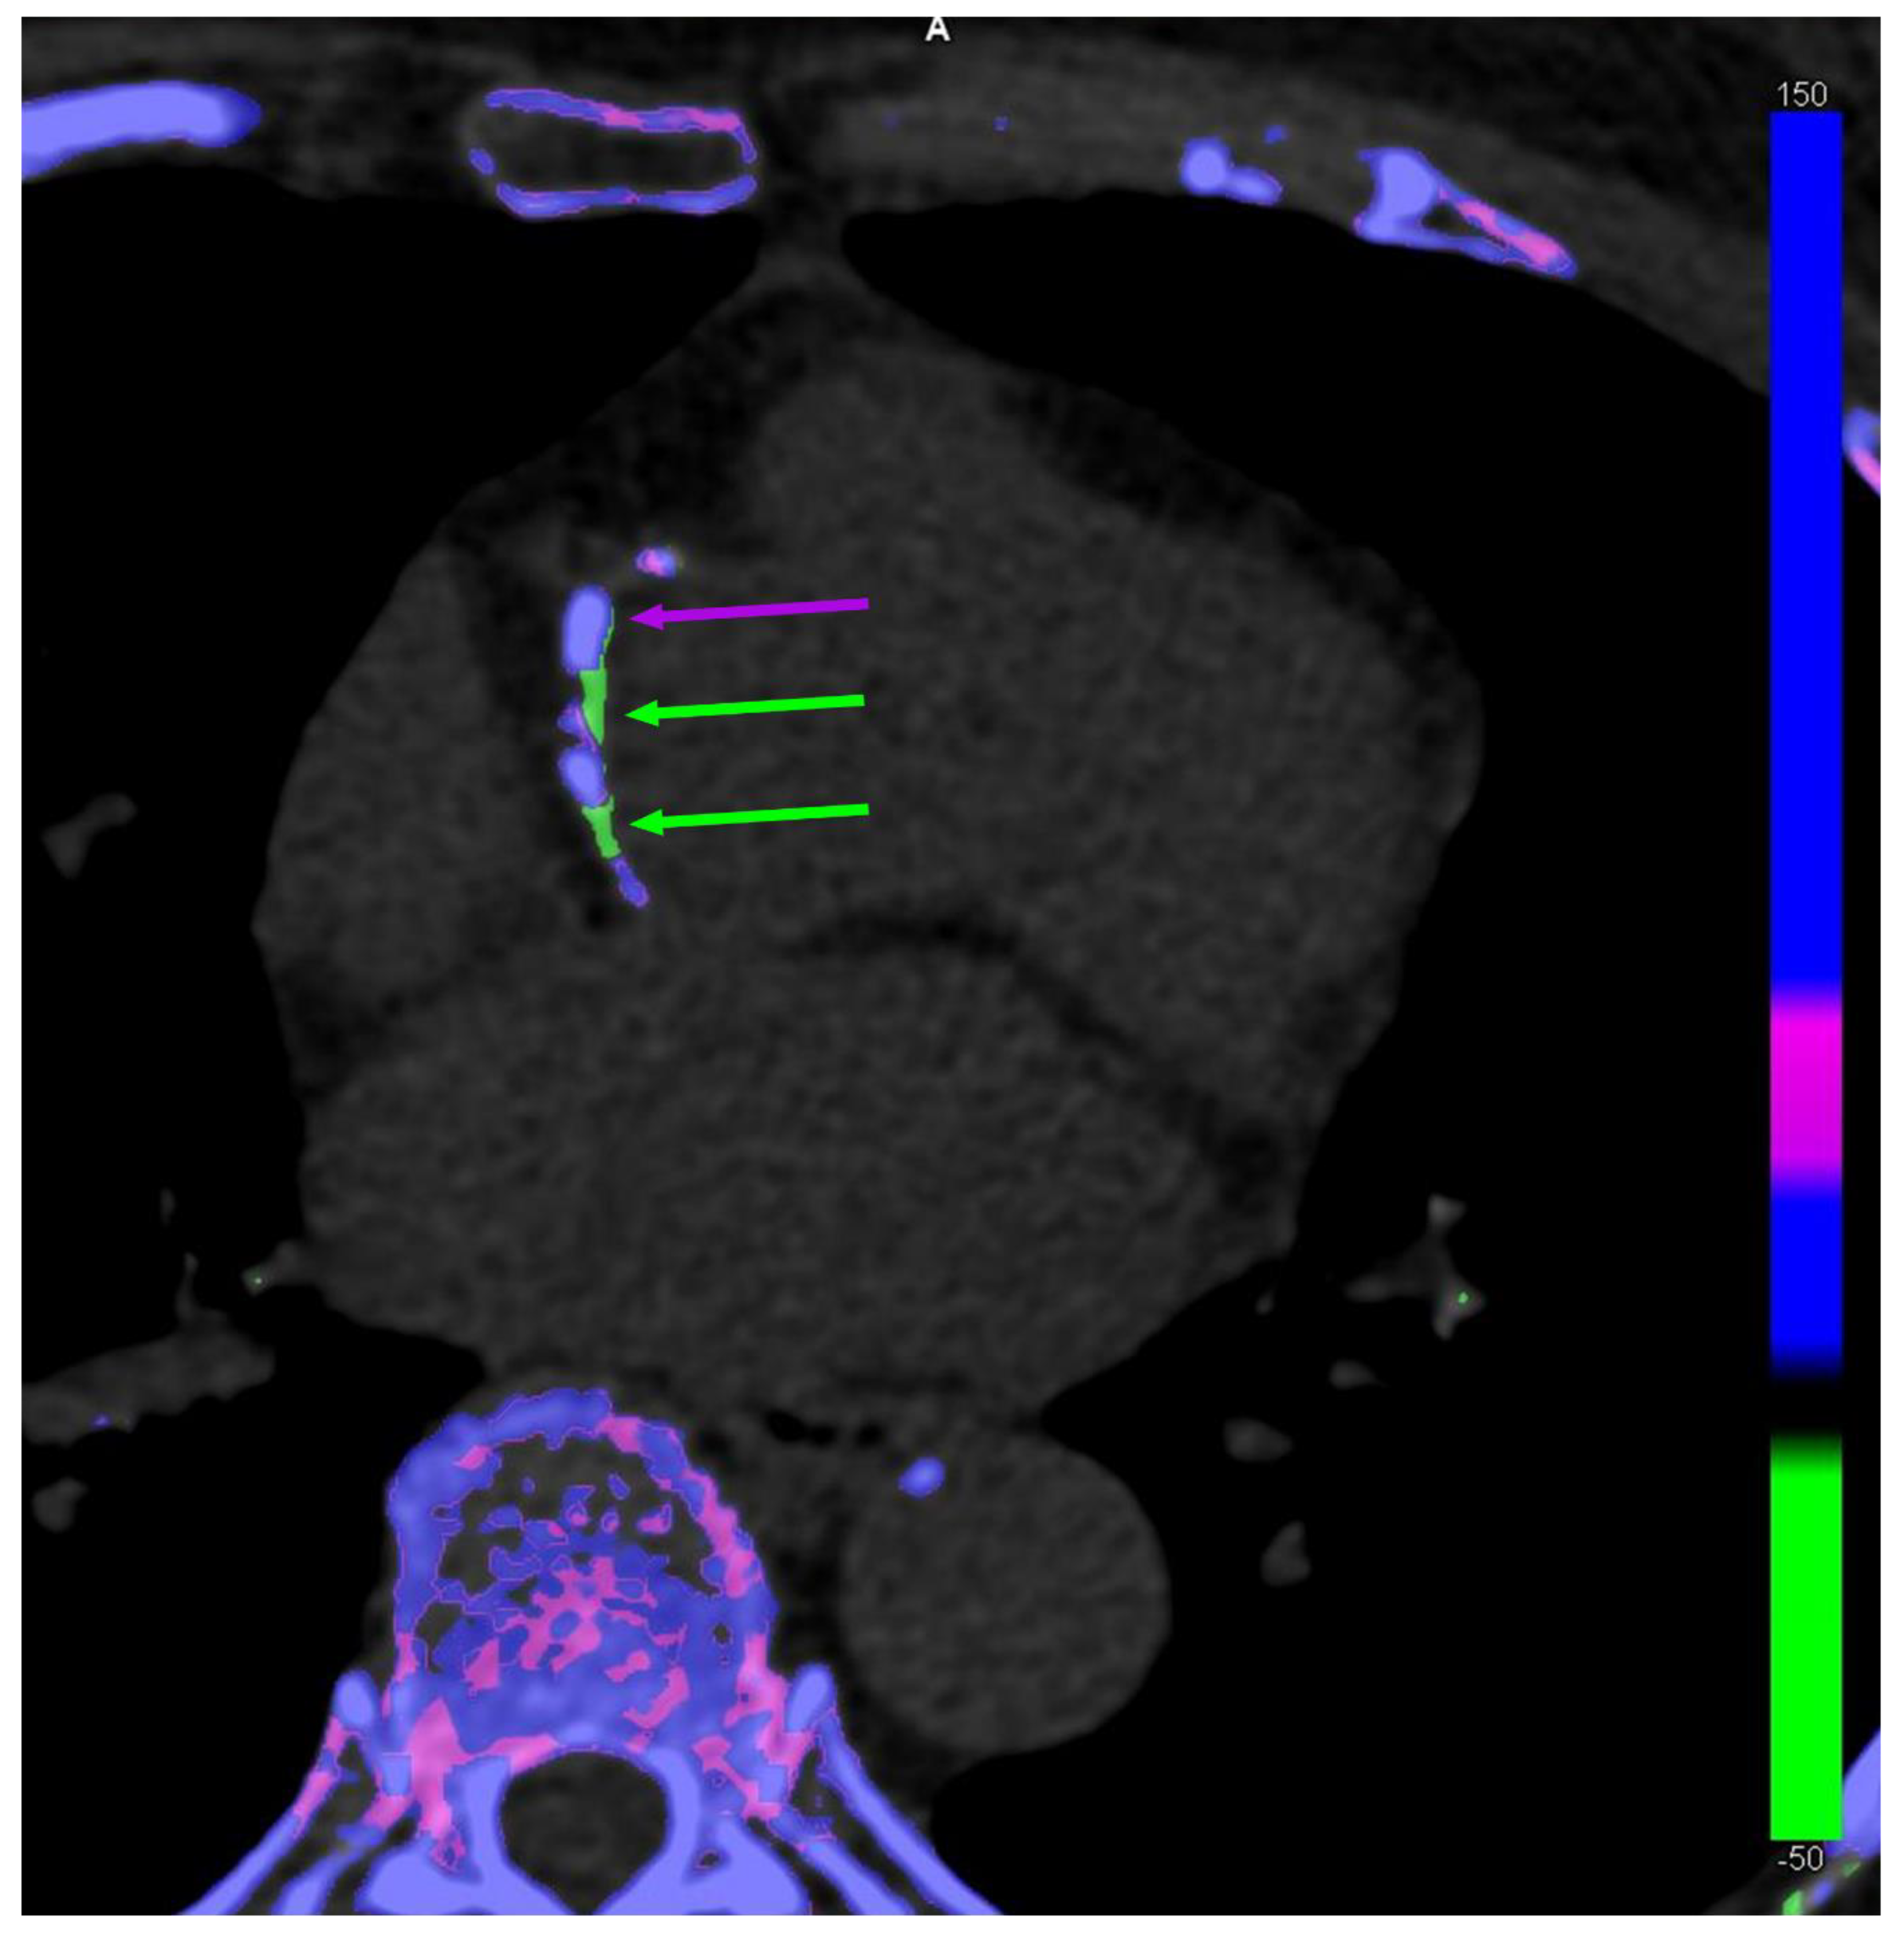

2.2. Imaging Evidence: The Debate on the Evidence Gathered with DECT

- Pascart, T.; Carpentier, P.; Choi, H.K.; Norberciak, L.; Ducoulombier, V.; Luraschi, H.; Houvenagel, E.; Legrand, J.; Verclytte, S.; Becce, F.; et al. Identification and characterization of peripheral vascular color-coded DECT lesions in gout and non-gout patients: The VASCURATE study. Semin. Arthritis Rheum. 2021, 51, 895–902. [Google Scholar] [CrossRef] [PubMed]

| Pascart T. et al. [24] | 2021 | 126 patients | Popliteal arteries | No | Dual-energy CT | Non-invasive (DECT parameter analysis) |